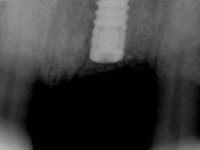

Male patient, 55 years old, smoker. Presented to our dental appointment with a dental implant placed in the area of tooth 21. The gingival architecture in the area lack interdental papilla and showed a vertical deficiency of the soft tissue. Adjacent teeth had significant root exposure.

The angulation of the dental implant did not allow for a screwed prosthesis. Thus, an anatomical abutment was used and the crown margin was milled 1mm infragingival, to allow the removal of the cement. The prosthetic component included a ceramic part emulating the crown and the root of the adjacent teeth, and a gingival part to compensate the soft tissue deficiency. Periodontal surgery to regenerate soft tissue in a vertical deficiency is complex and unpredictable, hence this prosthetic option. Although unconventional, this rehabilitation was well accepted by the patient, easy to perform and proved to be aesthetically satisfying and stable over time.